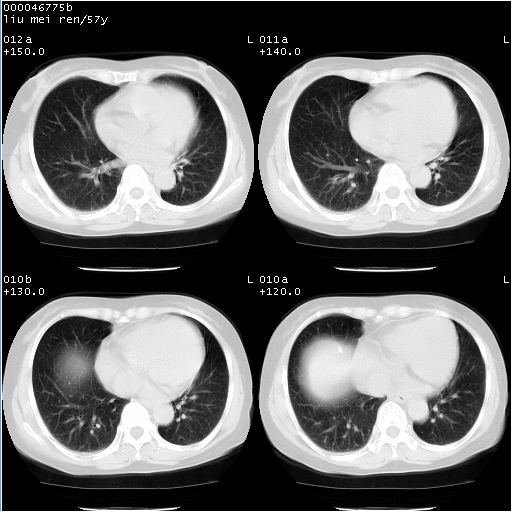

患者 女,57岁。因车祸受伤,其家属要求行“全身ct检查”。平素健康。

胸部ct轴位平扫(层厚10mm,螺距1.5,重建间隔10mm),图像如下: